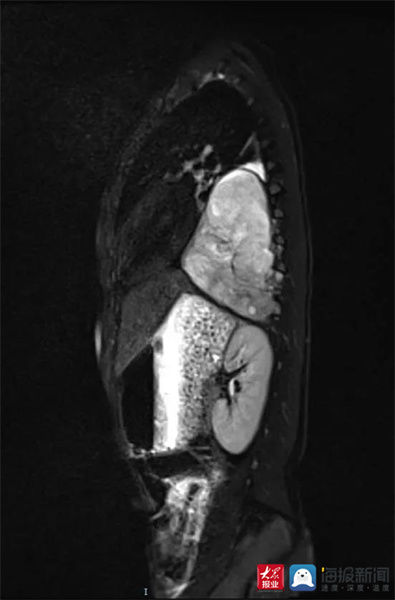

远远住院后,儿童外科医师立即给他完善各项相关检查,胸部MRI平扫结果显示肿物与周围器官组织联系紧密。

肺CT检查(李庆浩 供图)

尽快手术是唯一出路!儿童外科主任李庆浩表示,由于肿瘤与胸主动脉、心包、肺等器官紧密纠缠,手术难度很大,要成功实施手术,如何精准掌握肿瘤的侵袭范围,精巧分离周围器官和肿瘤成为关键。